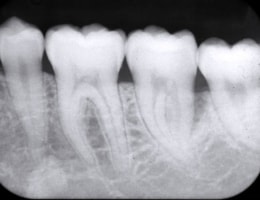

当院のデジタルレントゲンは、

従来のフィルムを使用したレントゲン撮影に比べ、

人体に受ける放射線の量を、約1/4~1/10に抑える事が可能です。

照射時間がかなり短く、安心安全です。

大きなパノラマレントゲンは歯並びなど、全体像をつかむことにも有効的ですが、

現状を詳細に把握するため、小さいレントゲンを10枚撮って診断・治療をしております。

これにより歯石、歯周ポケット等も詳細に把握でき、緻密な治療を提供することが出来ます。